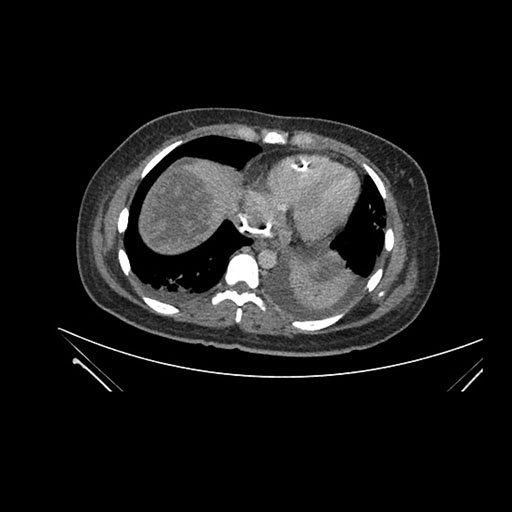

Imaging Analysis

Look through the patient's CT scan to identify any areas of concern for the necessary procedure.

Axial Venous

Based on initial findings, which issue(s) would you be most concerned about?